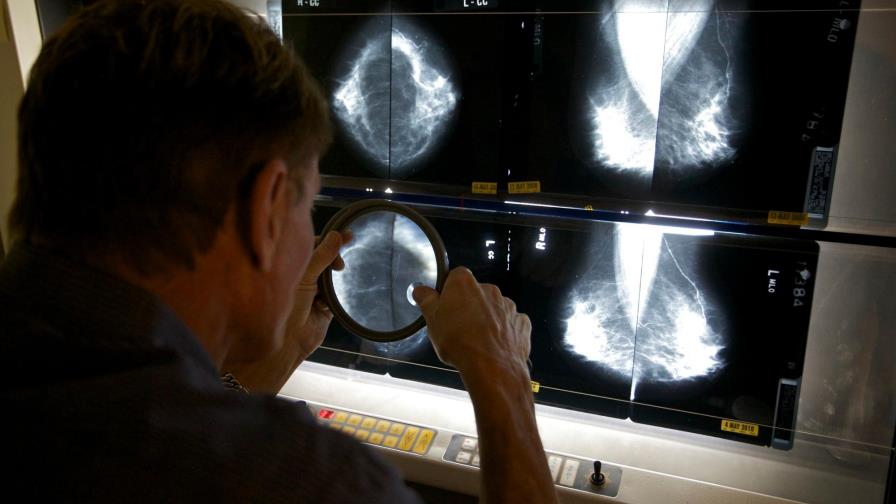

Riesgo de cáncer de seno por hormonas duraría décadas, según estudio

Las mujeres que utilizan ciertos tipos de hormonas luego de la menopausia mantienen un alto riesgo de desarrollar cáncer de seno casi dos décadas después de dejar de tomar las píldoras, sugieren los resultados de largo plazo de un amplio estudio financiado por el gobierno.

La principal parte del estudio fue suspendida en 2002 cuando los investigadores vieron con sorpresa más casos de problemas cardiacos y cáncer de mama entre las mujeres que consumían hormonas. A las mujeres se les aconsejó que detuvieran el tratamiento, pero los médicos han seguido estudiándolas y tienen información sobre cerca de dos tercios de ellas.

Con aproximadamente 19 años de seguimiento, se presentaron 572 casos de cáncer de seno en mujeres que consumieron hormonas contra 431 que ocurrieron en aquellas que ingirieron placebos. Ello representa un 29% más de probabilidad para desarrollar la enfermedad entre las mujeres que utilizan hormonas.